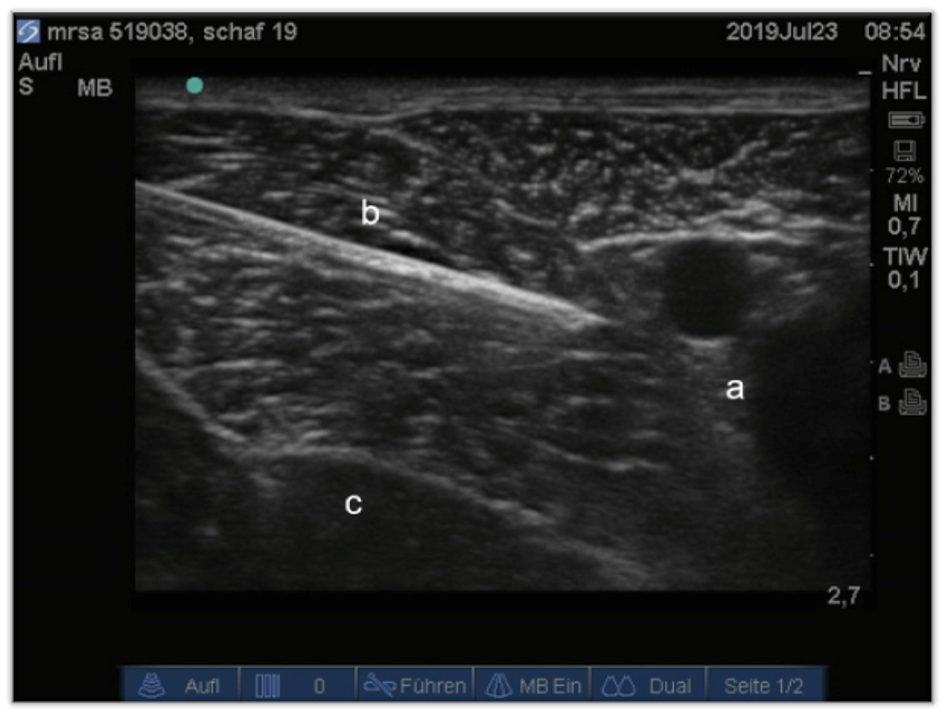

Analgesic efficacy of ultrasound-guided block of sciatic and femoral nerves in experimental sheep (Ultrasheep)

Current anaesthesia protocol at the ARI for orthopaedic hindlimb surgery in sheep includes epidural anaesthesia. Possible complications with an epidural analgesia are urine retention, neural damage, neuritis and temporarily loss of motor function in both hindlimbs. Nevertheless, it is very important to use local analgesia in order to save on anaesthetics and thus reduce their side effects. Therefore, in this study we investigated another protocol for local analgesia: the peripheral nerve block. To provide local analgesia in the operated hind limb we performed an ultrasound-guided block of the sciatic and femoral nerve and compared the analgesic efficacy of the nerve blocks with the epidural analgesia.

Ultrasound-guided peripheral nerve block is a reliable technique in sheep. There was no difference in analgesic effect of epidural and peripheral nerve block. A benefit of the peripheral nerve block is the earlier return to mobility in the recovery period since only the operated leg is motorically restricted.